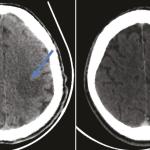

Innovations en oncologie

La prise en charge des cancers repose sur une approche multidisciplinaire associant les expertises complémentaires des oncologues et des médecins non oncologues. Des avancées en imagerie médicale aux nouveaux standards thérapeutiques en oncologie médicale, en passant par la chirurgie, la…